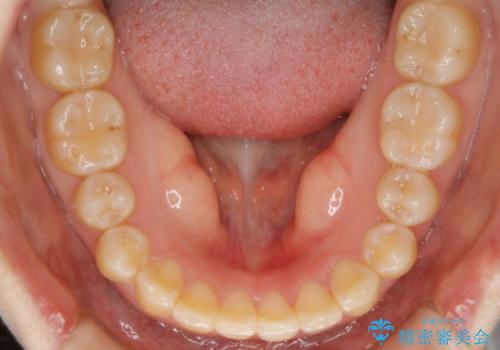

【非抜歯】ガタつきと歯軸を正して長持ちする歯へ

- 歯のガタつきと噛み合わせの改善を主訴に来院されました。

非抜歯で、少量の奥歯の移動と歯列の拡大・IPRを駆使して主訴を改善するための治療計画を立案しました。